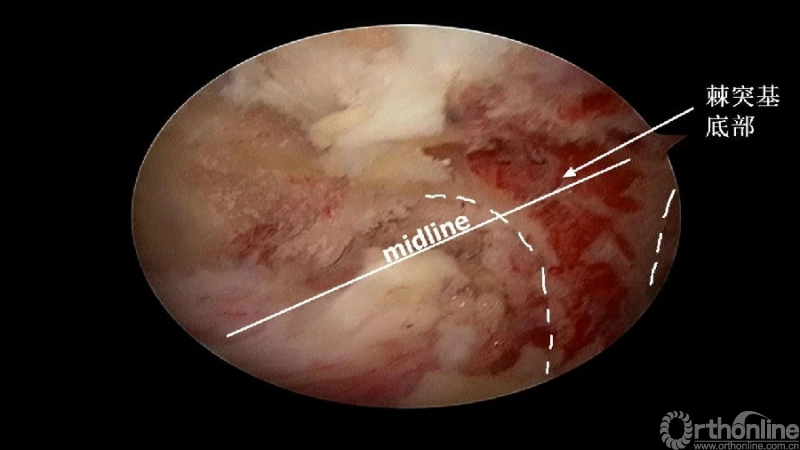

颈椎内镜下单侧入路双侧减压(ULBD)中,减压的难点还是在于识别棘突与椎板的移行部位及对侧结构的显露。

临床上,0°镜子绝对是颈椎UBE的最好用的镜子,但是30°的镜子对侧中线结构的显露及对侧结构的显露具有更广角的视野。在进行同侧减压之前,中线结构的显露是关键。

1. 术中如何确定中线?